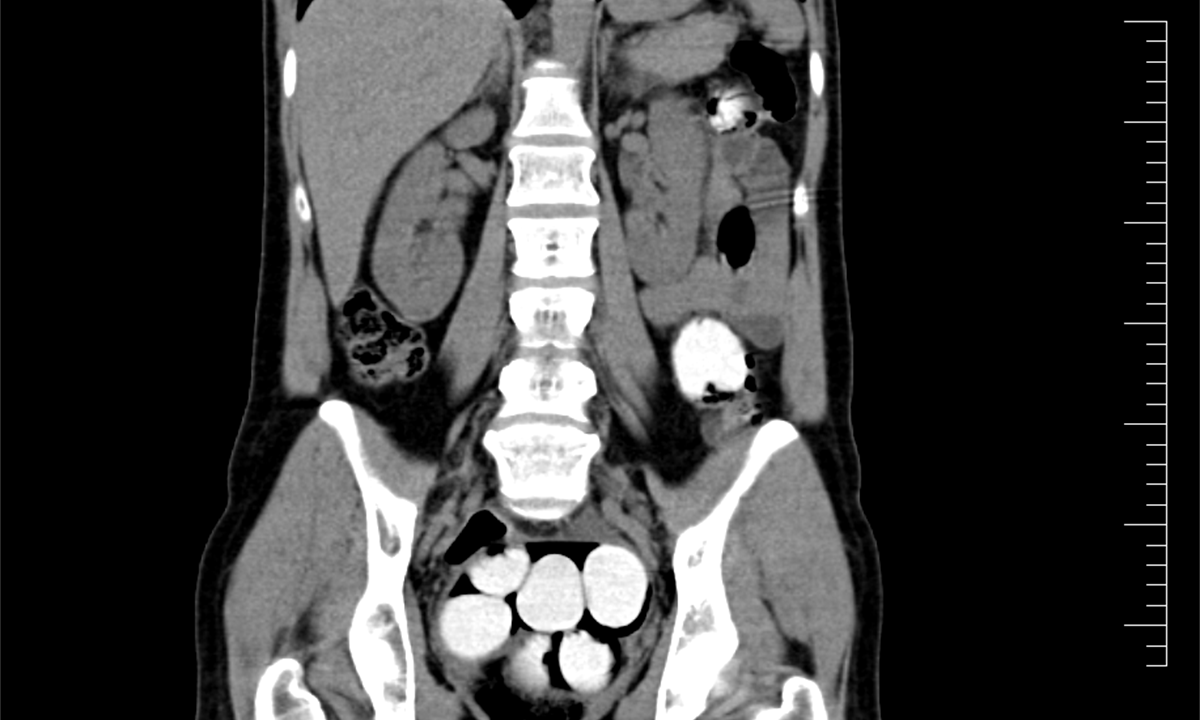

Ke kontrole byl polykač celníky vytipován na základě provedené rizikové analýzy daného letu. Prvotní podezření na pašování drog celníkům potvrdily kontrolní stěry z rukou pašeráka.  Při důkladné kontrole jeho zavazadel a osobní prohlídce nebyly drogy nalezeny, proto bylo provedeno následné CT vyšetření, které podezření potvrdilo.

Postupně z těla pašeráka vyšlo 112 kontejnerků naplněných bílým práškem. Chemická látka při provedení detekční zkoušky pozitivně reagovala jako kokain. Celková hmotnost všech kapslí je více než 1,2 kg. Určení vlastní hmotnosti a druhu zajištěné drogy je předmětem další odborné expertízy. Podle zkušeností celníků se s největší pravděpodobností jedná o velmi koncentrovaný kokain. Zda byla droga určena na český trh nebo k distribuci v jiné zemi, je předmětem dalšího šetření.